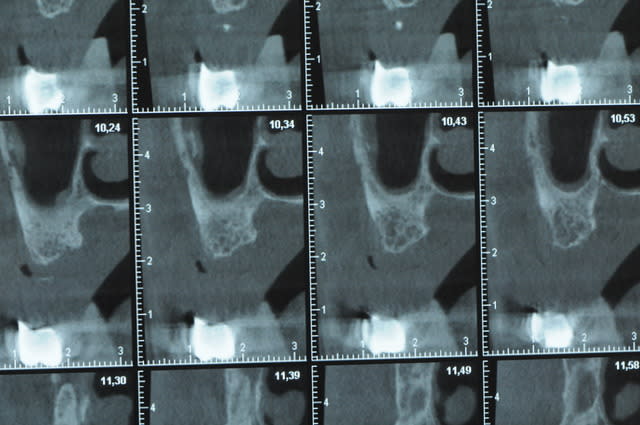

j'ai besoin de 4 implants au maxillaire pour faire tenir son complet.

dans la zone postérieur, pas de problème, mais devant, c'est une autre histoire.

la corticale a l'air tiptop, par contre en cas d'expansion il faut eventuellemnt augmenter le nombre d'implant à 6 pour compenser eventuellement le manque d'epaisseur 'avis personnel)

Je suis sceptique sur la gestion de ce cas par bone splitting puisqu'il met parait très difficile d'obtenir un volume osseux peri-implantaire crestal suffisant et satisfaisant.

+1 Olive, ce serait à mon avis plus prédictible avec des greffes. Je doute qu'on puisse obtenir suffisamment d'os en vestibulaire et en palatin des implants en splittant une crête aussi fine.

Ce n'est pas vraiment un consensus mais plutot du bon sens. Si tu as une crête en profil de lame de couteau cela signifie que tu as une fusion des corticales vestibulaire et palatine et donc absence de spongieux, ce qui comme tu le sais n'est pas indiqué en implanto (cj os de marbre par exemple)

Il me semble que Palti ou encore Szmukler-Moncler recommandent un minimum de 2-3mm. Si c'est plus fin, greffe d'apposition et GBR.

Dans ton cas il te faudrait abaisser la crête de 3 bons mm pour arriver à cette épaisseur.

Une petite étude de ton cas D57

Sous réserves bien sur de voir l’animal en vrai

Les zones exploitables radiologiquement parlant:

Coupes implant

2,3 40100

4,96 35130 avec sinus lift mais difficile

5,25 35150

6,02 35130

6,78 35115 après réduction de hauteur de crête

7,26 35115 après réduction de hauteur de crête

8,51 35150

10,43 40115 ou 50115

11,10 40115

Ce qui nous fait 9 implants possible évidement avec un comblement de sinus on augmenterait encore les zones implantable mais ce n’est pas le but recherché, avec 8 (4+4) il doit être possible de faire une belle barre support de complet